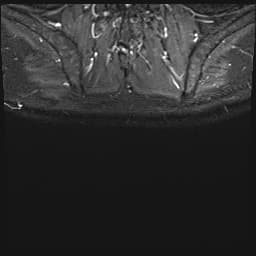

Axial Gradient Echo

- Có các ổ dịch ngấm thuốc viền (peripherally enhancing collections) xung quanh khớp cùng đòn mỏm cùng phải.

- Các ổ này đi kèm với tín hiệu bất thường ở tủy xương trong mỏm cùng (acromion) và đầu xương đòn (distal clavicle), cùng với các ổ ăn mòn vỏ xương (cortical erosions) ở xương đòn.

- Ngoài ra, thấy nhiều ổ dịch ngấm thuốc viền kích thước khác nhau nằm trong mô dưới da và các mặt phẳng cơ.

- Các ổ này lan vào các cơ thang (trapezius), cơ delta (deltoid) và cơ ngực lớn (pectoralis), đi kèm tín hiệu bất thường và ngấm thuốc thì tĩnh mạch cửa (post-contrast enhancement) ở các cơ lân cận và mô dưới da phía trên.

- Chụp cộng hưởng từ (MRI) là phương tiện ưu tiên để chẩn đoán sớm, cho phép đánh giá tràn dịch khớp, ngấm thuốc màng hoạt dịch, tổn thương mô mềm quanh khớp và các thay đổi xương kèm theo.

- Trong trường hợp này, sự hiện diện của các ổ dịch ngấm thuốc viền tập trung quanh khớp cùng đòn mỏm cùng, kết hợp với bất thường tín hiệu tủy xương và các ổ ăn mòn vỏ xương ở xương đòn và mỏm cùng, hỗ trợ chẩn đoán viêm khớp nhiễm trùng. Viêm tủy xương kèm theo (osteomyelitis) cũng là một khả năng rất cao.

- Các ổ dịch lan rộng trong cơ và dưới da, ảnh hưởng đến các cơ thang, cơ delta và cơ ngực lớn, biểu hiện cho sự lan rộng của nhiễm trùng với sự hình thành nhiều ổ áp xe – đây là một biến chứng đã được ghi nhận trong nhiễm trùng kéo dài hoặc tiến triển nhanh.